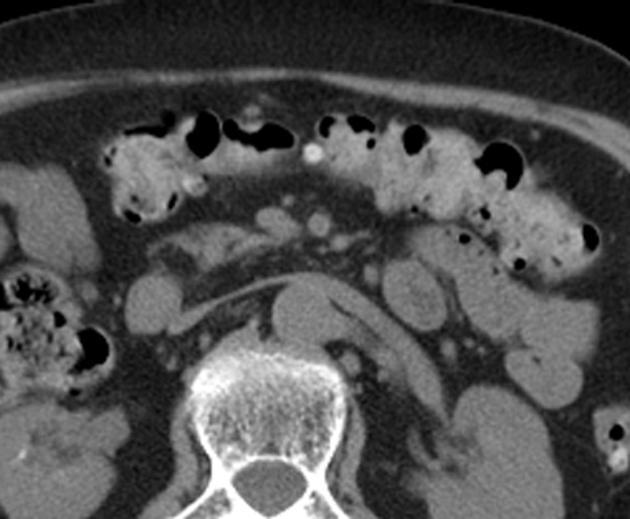

Aspect de epaissisement

et stenosant de la paroi de ileon dans tuberculose

ileo-caecale( fleche rouge ) Image TDM en coupe axiale |

Epaissisement hyper-densite

de la paroi de ileon . Image TDM en coupe axiale |